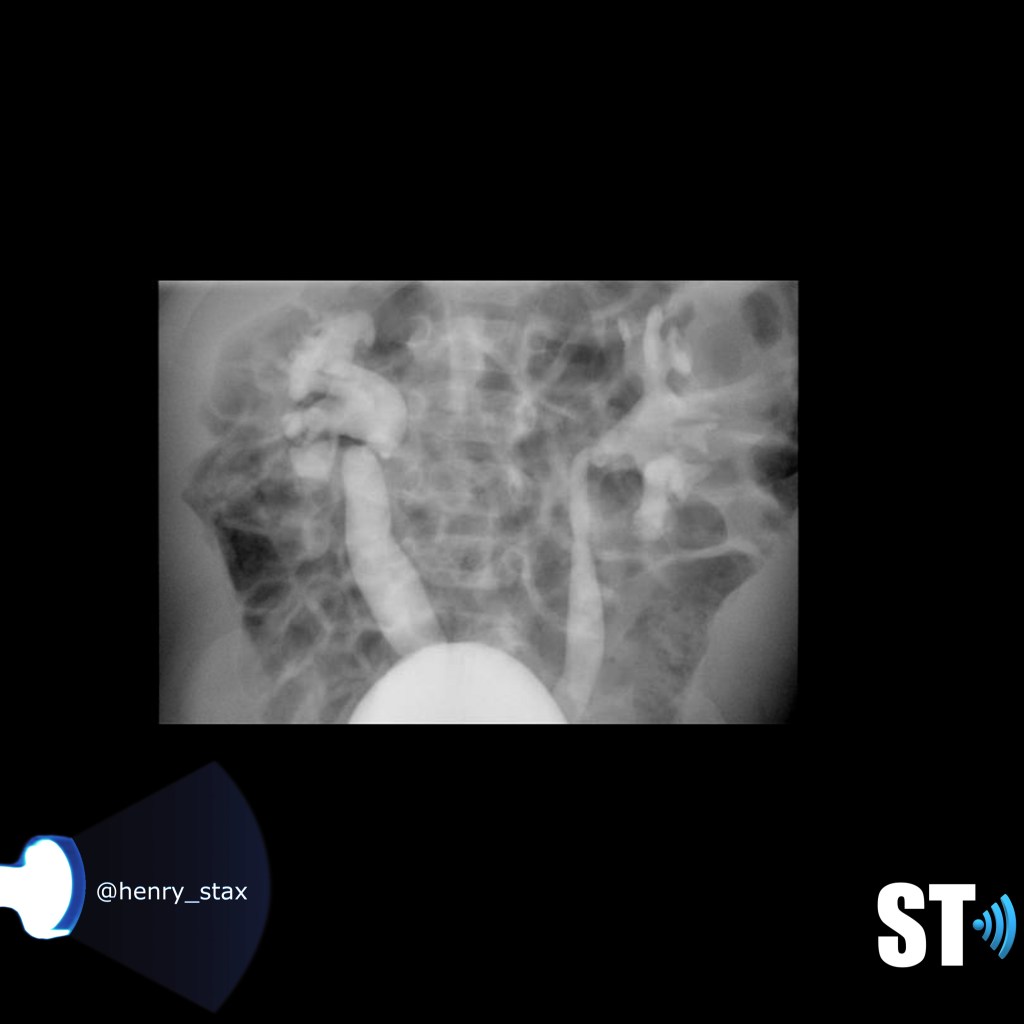

Xanthogranulomatous Pyelonephritis

(Xantho – yellow/Granuloma- collection of macrophages)

Rare form of chronic pyelonephritis usually caused by proteus mirabilis or E.coli. It usually occurs in the presence of long term obstruction. The kidney is non functioning, there is typically a calculus involved, usually a staghorn. A mass may be present that can be mistaken for a renal cell carcinoma, the microscopic features are lipid-laden foamy macrophages accompanied by chronic and acute inflammatory cells.